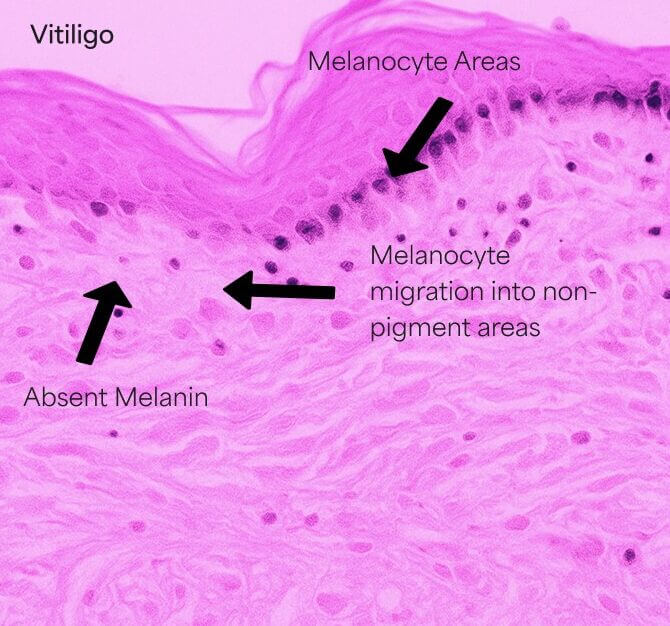

Hypopigmented Patches

Hypopigmented patches occurs when pigment-producing cells (melanocytes) die or stop producing melanin.

The involved patches of skin become lighter or white. It’s unclear exactly what causes these pigment cells to fail or die.

It may result from an autoimmune disorder, hereditary factors, or trigger events like stress, sunburn, or chemical-induced skin trauma.

How it works

- Induce the activation, migration, and/or proliferation of melanocytes into hypopigmented areas at the dermal-epidermal(DEJ). This shallow dermis area is the target depth.

- Also, mechanical trauma stimulates the melanocytes migration from the pigmented areas to unpigmented areas.

- Microneedling may increase the number of pigment cells and stimulate more pigment production

- Studies in literature indicate that 6 or more treatments may be necessary to begin to see improvement